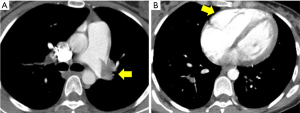

A 33-year-old female at 28 weeks pregnant presented to the Massachusetts General Hospital emergency room with sudden onset of dyspnea and pre-syncope. Her heart rate was 115, blood pressure 107/52, respiratory rate 24 and she was hypoxic with oxygen saturation of 88% on room air. With immediate concern for acute PE, a CT pulmonary angiogram (CTPA) was performed and demonstrated a large volume of bilateral main pulmonary arterial embolism and evidence of right ventricular (RV) dilatation (Figure 1). Cardiac biomarkers assessing for evidence of RV strain were elevated with Troponin T 0.16 and NT-BNP 550. Lower extremity ultrasound demonstrated no evidence of deep vein thrombosis (DVT).

This multi-disciplinary organization was orchestrated within 30 minutes of the PERT activation and through a single PERT group conference call. With this planning in place, the patient was brought to the catheterization lab for placement of bilateral EKOS catheters. Via these catheters, she was treated with 12 mg of tPA over 5 hours. Prior to removal of the catheters, she was noted to have a decrease in her PA systolic pressures from 50 mmHg at the time of the procedure to 32 mmHg at 5 hours. No maternal complications or fetal distress occurred during or after the procedure. She was discharged on enoxaparin (1 mg/kg twice daily) on post-procedure day 3. Repeat echocardiogram performed 2 weeks after her hospitalization demonstrated normalization of her right ventricle (Figure 3). The infant was delivered without complications at 39.5 weeks, and the patient and infant continue to do well.